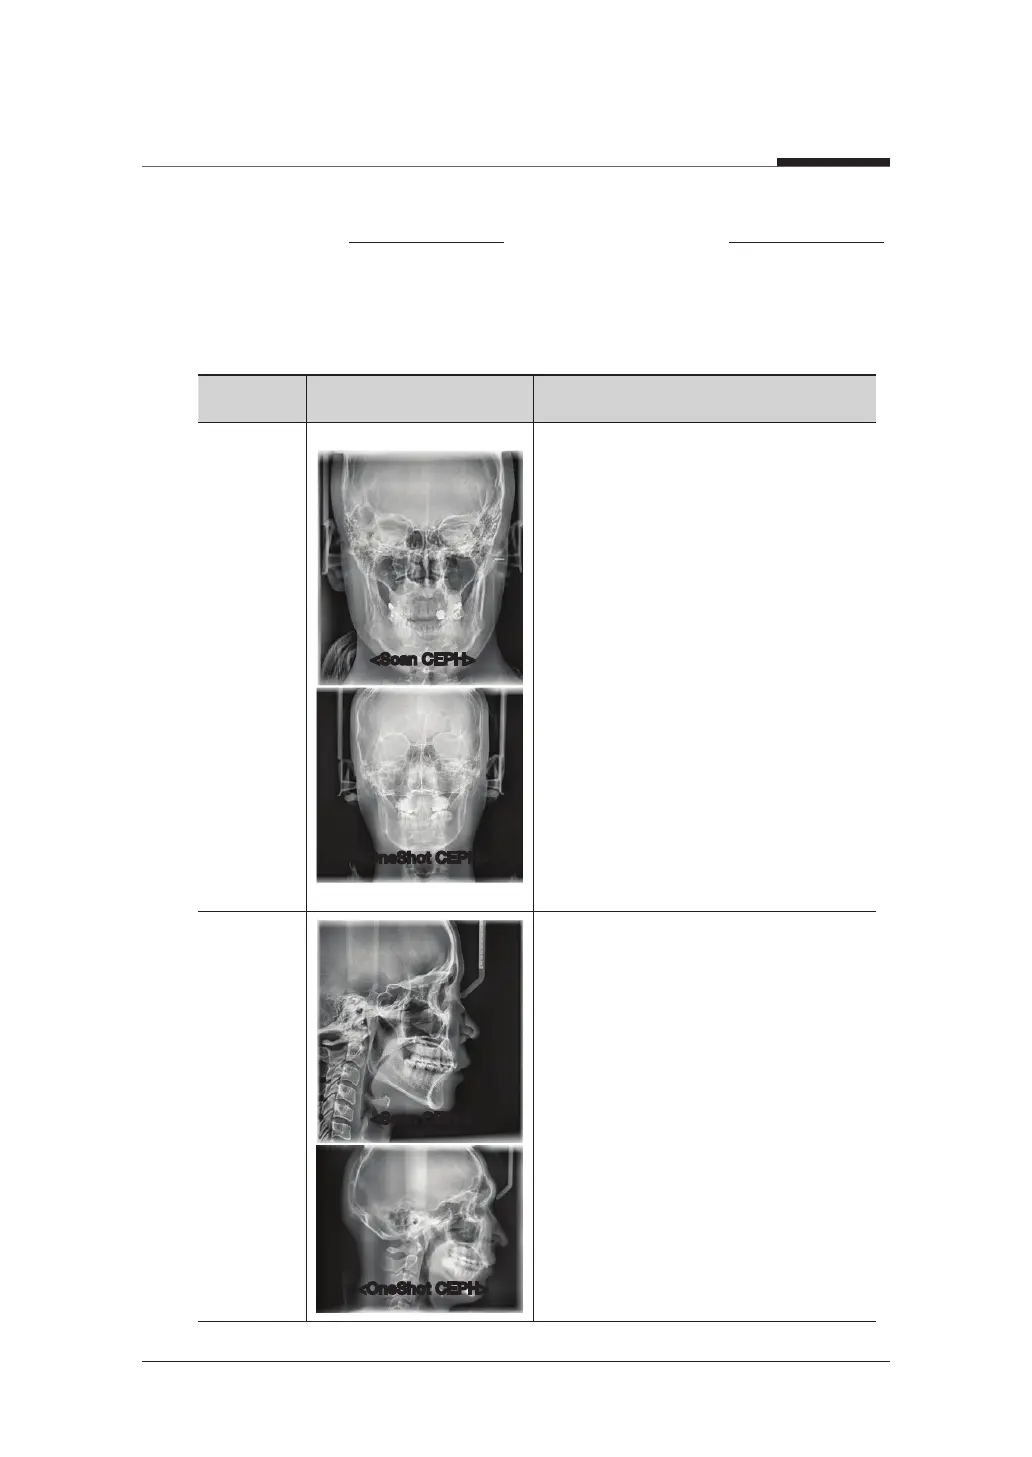

Examination Image Description

PA

The radiation is directed from the

posterior of the skull to the anterior.

Use to examine cranial diseases,

trauma and congenital malformations.

Used to assess the growth of lateral

side of the face. It is also useful to

examine the ramus mandibulae, the

posterior region of the third largest

molar in the lower jaw, and the side

wall of the maxillary sinus, and the

frontal sinus, antrum ethmoidale,

olfactory pits and optic disc pits.

Measure the angles formed by the

Lateral

Study craniofacial disease, trauma

and congenital malformation and

examine the soft tissue in the

otorhinolaryngological area, sinus and

hard palate.

connecting lines between the cranial

measurement points to further assess

the growth of the facial region. It's

widely used in Orthodontics and Oral

and Maxillofacial Surgery.

<Scan CEPH>

<OneShot CEPH>